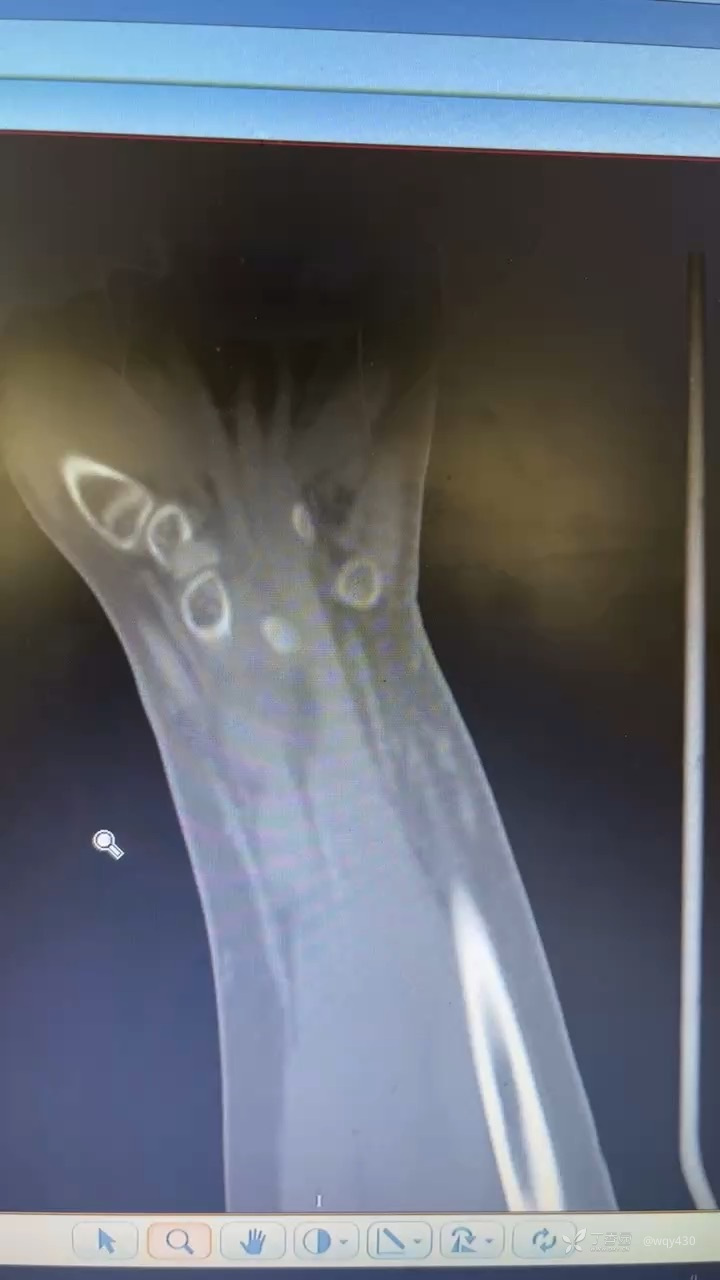

患儿,男,13岁,摔伤致伤,行手术治疗克氏针固定,术后2月骨折愈合不良,求进一步治疗方案:

术后

下面大约术后8周,摄片后拔出克氏针,